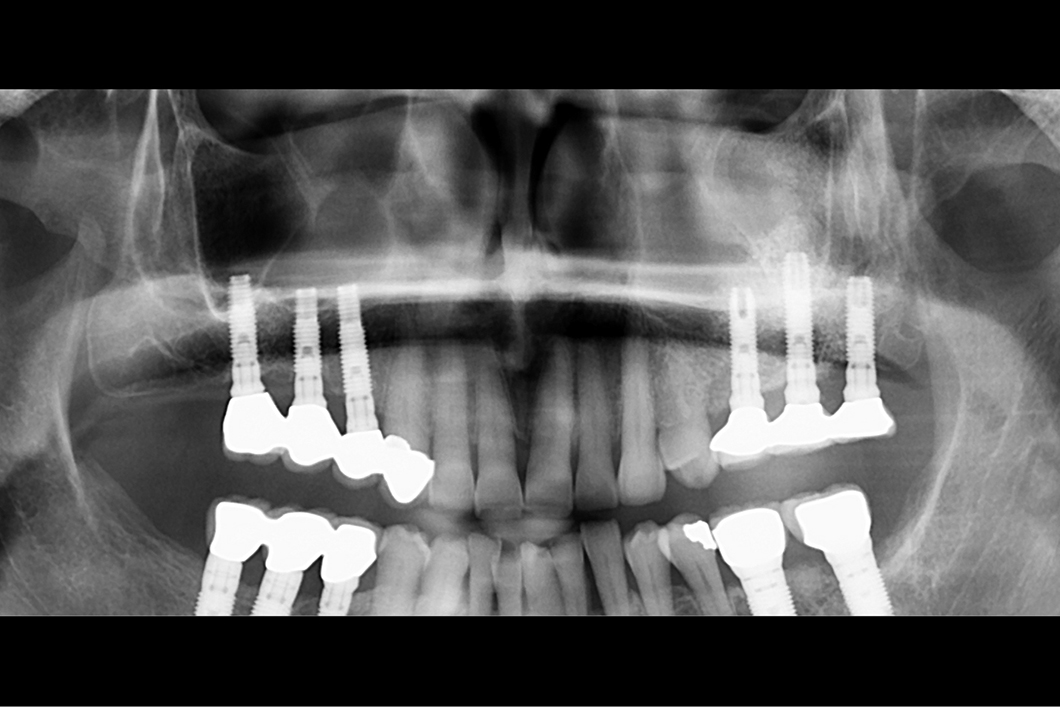

Eine 62-jährige gesunde Patientin wurde zur Extraktion von Zahn 16 an das Schwartz-Arad Chirurgiezentrum überwiesen. Die Patientin wurde 1997 behandelt und über einen Zeitraum von 20 Jahren nachkontrolliert. Interessant ist hier die Region 16. In dieser Region war der 1. Molar aufgrund eines Paro-Endo-Defekts nicht mehr behandelbar. Die Zähne 14 und 15 fehlten ebenfalls. Die vorhandene Brücke erstreckte sich von 13 auf 16. Der verfügbare Alveolarkamm war aufgrund der Pneumatisation der Sinushöhle und der Endo-Paro-Läsion des Zahnes nicht ausreichend für eine Implantation. Die Patientin wünschte eine festsitzende prothetische Restauration. Die klinische Herausforderung war die vertikale Rekonstruktion des Kieferkammvolumens über eine Sinusboden-Augmentation und eine gleichzeitige Ridge Preservation im Zuge der Extraktion von Zahn 16 für eine spätere Implantation.

- Perfekte prothetische Situation bei Nachkontrolle nach 20 Jahren.

Dieser Fall, mit einer Nachkontrolle über 20 Jahre, ist nur ein Beispiel für die vielen Patienten mit insuffizienten Alveolarkämmen, die im Schwartz-Arad Chirurgiezentrum mit Geistlich Bio-Oss® behandelt wurden. Die Sinusboden-Elevation mit Geistlich Bio-Oss® und Geistlich Bio-Gide® ist ein langfristiger, vorhersagbarer Behandlungsansatz. Die Perforation der Schneiderschen Membran beeinflusste den Implantaterfolg nicht negativ, da sie mit Geistlich Bio-Gide® korrigiert wurde.